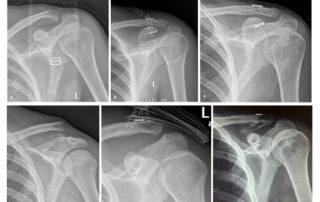

Σύγχρονες θεωρίες πώρωσης των καταγμάτων με βάση το ανοσοποιητικό μοντέλο

Δημοσίευση νέας έρευνας με την συμμετοχή του Γιάννη Τριανταφυλλόπουλου σχετικά με την επίδραση του ανοσοποιητικού συστήματος στα κατάγματα. Το πολυσυζητημένο -ελέω πανδημίας- ανοσοποιητικό μας σύστημα φαίνεται πως παίζει κυρίαρχο ρόλο [...]